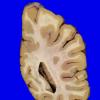

Neuronal Ceroid Lipofuscinosis (NCL) (11)